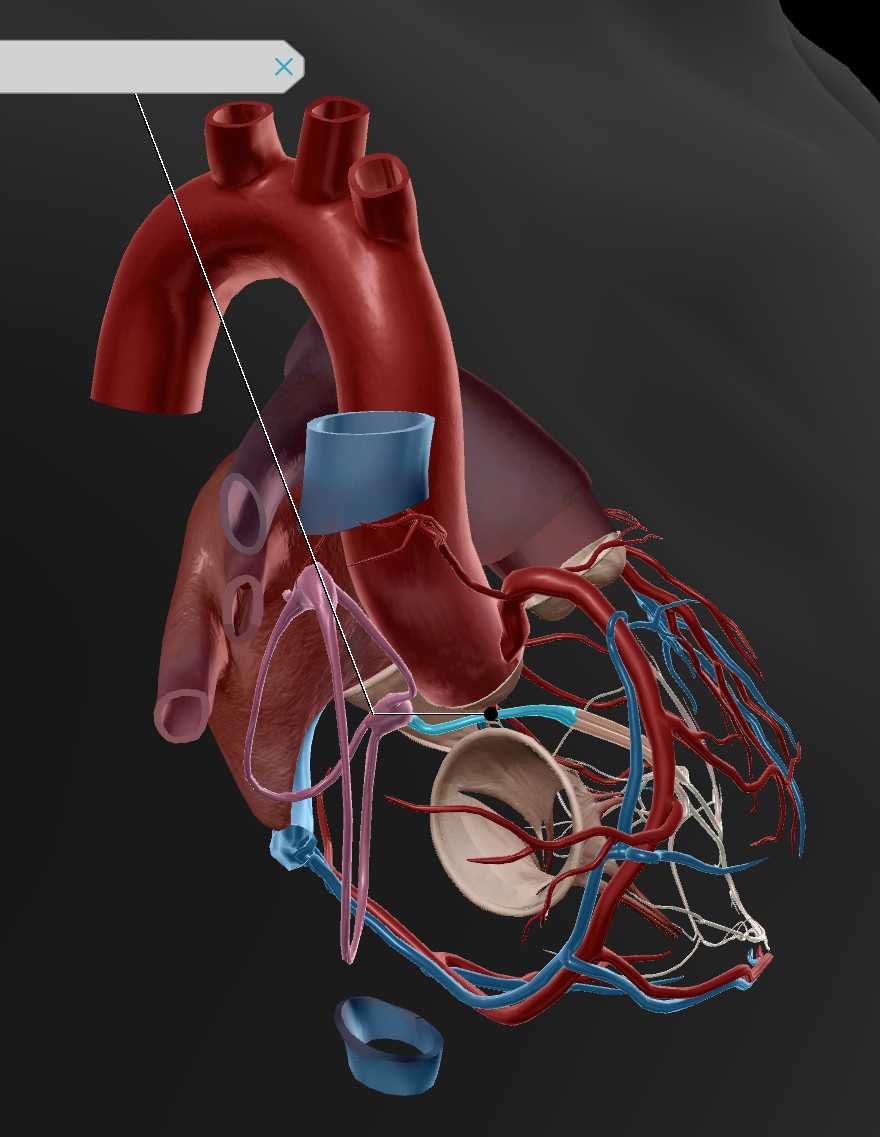

Inferior Vena Cava

Superior Vena Cava

Pulmonary Trunk

Anterior Interventricular Artery

Circumflex Branch

Coronary Artery

Aortic Arch

Brachiocephalic Trunk

Thoracic Aorta

Coronary Sinus

Anterior Interventricular Sulcus

Coronary Sulcus

Posterior Interventricular Sulcus/Artery

Coronary Veins

Marginal Branch

Circumflex Artery

Great Cardiac Vein

Pulmonary Artery

Pulmonary Vein